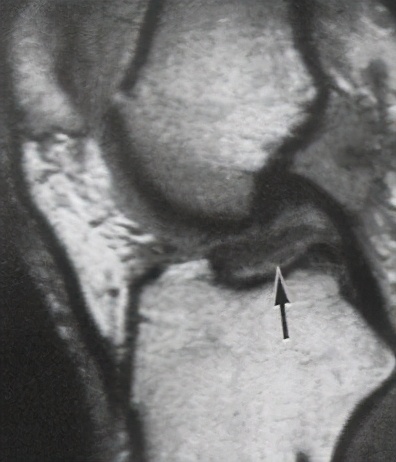

一般膝关节韧带损伤都有外伤病史,以青少年居多,男性多于女性,以运动员最为多见,受伤时有时可听到韧带断裂的响声,很快便因剧烈疼痛而不能再继续运动或工作膝关节处出现肿胀,压痛与积液(血),膝部肌痉挛,患者不敢活动膝部,膝关节处于强迫体位,或伸直,或屈曲膝关节侧副韧带的断裂处有明显的压痛点。高处跌落,车祸等直接*力暴**也可直接至韧带损伤或同时伴有骨折等其他损伤。韧带损伤常常合并膝关节半月板损伤。膝关节MRI检查可以辅助诊断,可以清晰显示出前、后交叉韧带的情况,还可以发现隐匿的骨折线及半月板损伤。下图左边是正常前交叉韧带,右边是损伤前交叉韧带

重建术前的 前交叉韧带 :

重建术前的 前后 交叉韧带损伤